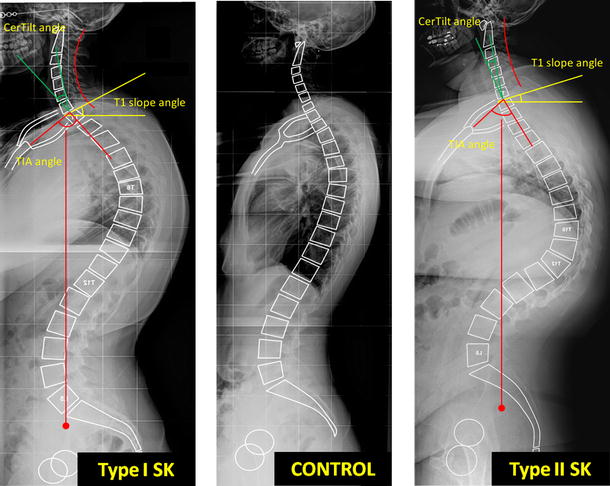

Cifosi oltre i 40°

misurata sulle rx in piedi T3 – T12z

Cifosi da Morbo di Scheuermann: Toracica

Cifosi da Morbo di Scheuermann: ToracoLombare

La cifosi da Scheuermann è una tipica cifosi o dorso curvo dell’adolescenza da distinguere dalla cifosi posturale per la sua peculiare rigidità con dolore. Tre o piu’ corpi vertebrali adiacenti sono cuneizzati. Tipiche alterazioni delle limitanti somatiche. Alla deformità si associa una rachialgia dorsale (dorsalgia meccanica), che costituisce spesso il sintomo che porta alla consultazione.